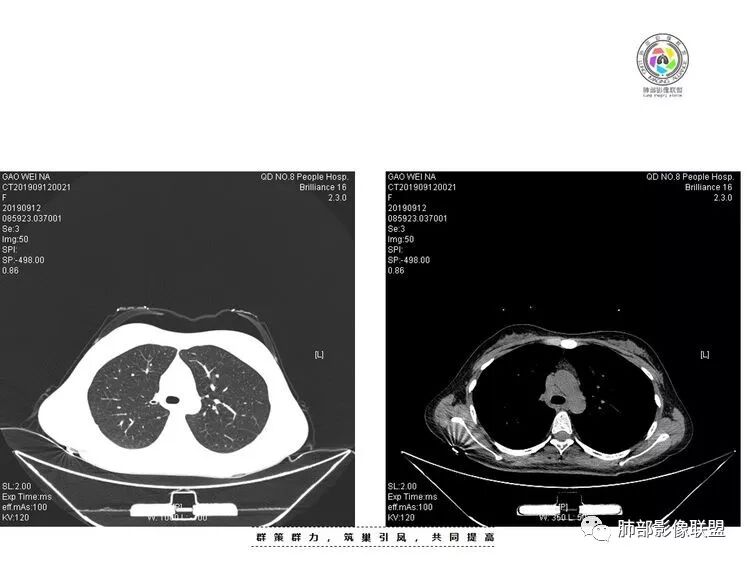

年轻女性,咳嗽咳痰(白黏痰)一月,加重一周,发热3天伴咯血。实验室:中性粒、CRP、血沉增高CT:右肺下叶不规则厚壁空洞伴散在树芽、小叶中心结节。空洞内壁光滑,似见液平。无胸腔积液及明显纵膈肿大淋巴结。给予左氧及美洛治疗12天复查CT,病灶明显吸收缩小。考虑感染没有问题。问题是单纯细菌感染还是结核感染?甚至二元?患者病史较长,临床与影像都有符合结核的表现,且左氧对结核治疗有效。因此,建议痰找抗酸杆菌,痰培养,并继续复查肺部CT。

青年女性咳嗽带血,右下背段厚壁光滑空洞伴坏死,周围渗出伴树芽征,氧氟沙星治疗后有病灶有吸收、新旧交替,考虑结核。

年轻女性,咳嗽咳痰一个月,加重一周,发热三天。实验室检查,白细胞,血沉,CRP增高影像,右肺下叶不规则厚壁空洞,内部光整,厚壁空洞周围伴有大量渗出及树芽征;抗炎治疗后空洞缩小,增强洞壁伴有坏死,考虑为炎性病变,结核可能性大

患者青年女性咳嗽、咳痰1月,加重1周,发热3天。患者1月前受凉后出现咳嗽,咳少量白色痰,1周前咳嗽加重,痰量增多,为黄白色黏痰,偶有痰中带血,轻微胸闷,近3天来出现发热,最高体温38.4℃,伴乏力,食欲下降。辅助检查:血常规白细胞及中性分类 血沉 CRP均增高。胸CT:右肺下叶前基底段实变病灶内可见空洞,洞内可见气液平面,病灶周围及右肺下叶背段可见树芽征 、结节。经抗感染治疗,基底段病灶较前缩小,背段病灶 融合 增大。考虑良性病变,空洞性肺结核合并细菌感染。

青年女性,亚急性病程,近1周加重,咳嗽,黄痰,痰血,发热,乏力,食欲下降。血沉,血白细胞,中性粒细胞升高。胸部CT:右肺下叶背段,基底段多发病灶,结节,树芽,实变,空洞,支气管似有狭窄。抗感染治疗后部分好转。考虑:肺结核合并支气管结核?

年轻女性,右肺下叶背段,腺泡结节,树芽征,厚壁空洞有液气平面,纵隔多发小淋巴结,气管前淋巴结中间有点状钙化。病人咳嗽一个月,最开始少量白痰。后面中度发热,痰中带血,黄白痰。抗炎空洞有吸收。左氧对TB是有效的。综合考虑肺结核。空洞不排除肺脓肿,结核合并细菌感染。鉴别诊断真菌(毛霉菌)

女,28,咳嗽咳痰(白黏痰)一月,加重一周,发热3天伴咯血。实验室:WBC,中性粒、CRP、血沉增高CT:右肺下叶背段不规则厚壁空洞伴液平,内壁光滑,临近胸膜牵拉、糊墙,近端引流支气管壁厚,周围肺野散在树芽、小叶中心结节、斑片伴肺气肿,纵隔及右肺门有淋巴结,治疗后病灶缩小;考虑结核伴感染。

青年女性,亚急性病程,呼吸道感染症状,影像:右肺下叶厚壁空洞,内壁光滑,似有液平,外缘分叶、收缩+膨隆,支气管树芽,腺泡结节,界限较为清晰,近端支气管增厚,纵隔淋巴结肿大,强化不均匀;抗感染治疗后,团块短期内似有缩小,背段结节略增大,考虑感染,第一个排除肿瘤,影像上更支持结核,临床进程上支持脓肿,不除外二元因素,结核并感染

青年女性,临床体征和实验室检查支持炎性改变,缓慢病程,急性发作; 胸部CT :右肺下叶不规则实变影合并空洞形成,厚壁,內壁光整,似有液平,周围见卫星灶,树芽征,小叶中心结节,小叶间隔增厚,粘液栓,抗炎治疗后病灶较前吸收好转,考虑炎性病变 , 结核合并细菌感染?

年轻女性,咳嗽,咳痰,低热,乏力,白细胞增高,血沉增快.CT病变厚壁空洞,内壁光滑,周围可见实变及多发结节及树芽征,叶间胸膜略增厚,凹陷,考虑感染性病变;综合考虑:肺结核合并细菌感染可能;抗炎,查结核菌。

患者青年女性,咳嗽、咳痰1月,加重1周,发热3天就诊。病程中偶有痰中带血。查血常规白细胞及中性分类、血沉、CRP增高。胸部CT:右肺下叶可见斑片实变、结节树芽及空洞影,背段为明显,洞壁光滑、内可见液平,且实变空洞区呈支气管爬树征。虽经抗感染治疗症状好转,病灶有吸收,但结合其病史达一月,抗感染使用喹诺酮类抗生素。综合考虑考虑良性病变,结核合并细菌感染可能性大。鉴别恶性及血管炎并感染。

29岁女性,既往体健。咳嗽咳痰(白黏痰)一月,加重一周(黄白痰),发热3天伴咯血。血常规:中性粒、CRP升高,血沉增高。CT:右肺下叶不规则厚壁空洞伴散在树芽、小叶中心结节。空洞内壁光滑,似见液平。无胸腔积液及明显纵膈肿大淋巴结。予左氧及美洛西林舒巴坦治疗12天,临床症状减轻。复查CT见空洞明显吸收缩小,增强见薄壁空洞,内有液平,引流支气管增厚。考虑感染;是单纯细菌感染还是结核感染?还是细菌合并结核?建议痰找抗酸杆菌,痰培养,并继续复查肺部CT,可完善支气管镜检查。

青年女性,有低热,咳嗽,白细胞稍高,血沉高,右下叶背段可见不规则形厚壁空洞,内壁光整,周围见小花小草样斑片簇状影分布,右下叶背段支气管增厚,似有空洞相连,抗感染性治疗后,右下叶斑片影较前部分吸收减少,右下叶背段空洞缩小,但周围斑片影较前进展,右下叶背段支气管壁增厚,变窄,常规考虑继发性肺结核可能,建议增强,支气管镜及痰检痰培,结核分枝杆菌检查。

年轻女性,咳嗽咳痰,右肺下叶见厚壁空洞伴液气平面,有树芽征,治疗后空洞变小,周围病灶增多融合,支气管壁增厚略有扩张,临床血象高,考虑结核合并细菌感染。

年轻女性:右肺下叶背段,基底段不规则厚壁空洞,内壁光滑,且内壁上有坏死组织,第一次有液气平面,边缘分叶、膨隆、平直,周围多发腺泡结节,树芽,内侧支气管有狭窄。抗感染治疗后空洞缩小,但腺泡结节变化不大,考虑:肺结核合并伴感染?

2.右肺下叶片状影、结节影、硬树丫。单发空洞伴液平,内壁规则,外壁较清楚。相关支气管壁增厚。

影像符合典型继发性肺结核,或者说结核它是之前已经存在的。

结核空洞相对薄壁且很少液平,如此明显洞内积液也会怀疑合并细菌等感染。

抗感染治疗后短期复查右肺病灶变化明显,部分病灶如空洞性病灶明显吸收,部分病灶稍有增大融合(如背段病灶)。

可以基本明确合并细菌感染,且变化部分不宜用结核感染解释。